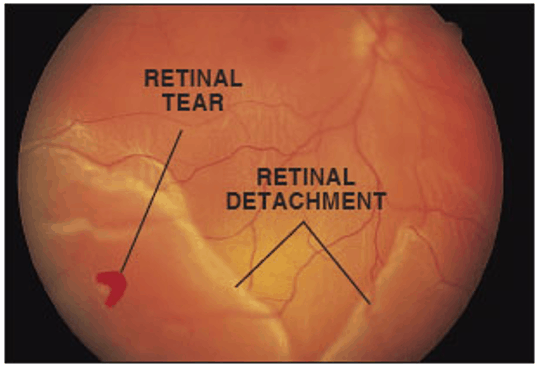

What are retinal detachments?

Retinal detachments are when the retina detaches from the inner wall of the eye. This occurs when retinal tears are not sealed early. This results in fluid traveling through the retinal tear and under the retina causing a detachment.

What are the symptoms of Retinal Detachment?

Symptoms of a retinal detachment include:

- Seeing a shadow in the side of your vision

- Seeing a gray curtain moving across your vision

- Sudden decrease in vision